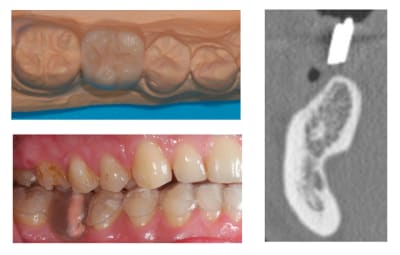

Bon je m'y colle, c'est pas le même niveau qu'olivier, mais ce sujet étant censé être pour les débutants je poste.

Patient 26 ans, à qui il manque 46, 25 et 26.

Pour l'instant je vous propose la partie préparation et mise en place de l'implant en 46, la suite peut être bientôt.

Dans l'ordre si le site veut bien, wax-up ( cirage pour céramik ;) ) , guide radio, et scan.

Photos pré-op, indicateur de direction en place et post-op.

Il s'agit d'un implant astra osseospeed de 5 mm de diamètre et 9 de long.

Prothèse prévue à 6 semaines.

puisque tu veux de la critique, impec (juste que je l'aurais mis à peine, mais vraiment à peine moins infra-osseux)

c'est à cause du profil de la crête, en fait l'implant est juxta-osseux en vestibulaire, par contre moi je le trouve ( légèrement ) trop distal.

il est prévu de faire une ROG.

simultanée avec Bio-Oss et os autogène.

oui membrane Bio-Gide en double épaisseur, avec rien.

avec Bio-Oss, os autogène et Bio-Gide et pose d'implant simultanée, peut être les photos le mois prochain.

bonne iconographie et bon travail, même si légèrement distal.

les critiques (dans le sens positif bien sur):

félicite le proth beau wax up.

j'aurais fait une petite expansion en bas ( tu t'en doute) pour retrouver un bombé vestibulaire et

j'aurais mis un peu plus long (12?)

pour le haut je me laisserais aller à une distraction (c'est vraiment un beau cas pour commencer) plutôt qu'une rog, mais tu as fait ton choix.